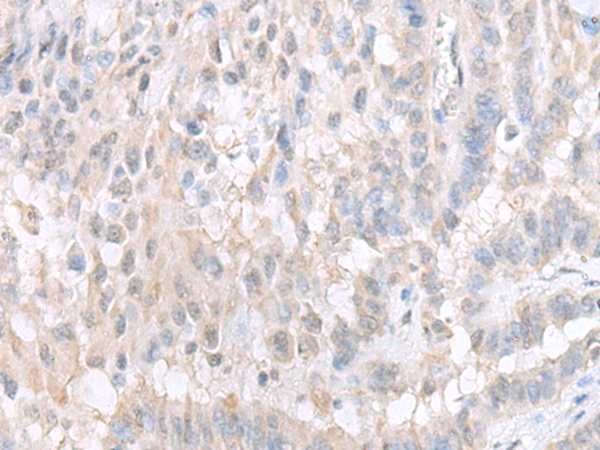

图片:

The image is immunohistochemistry of paraffin-embedded Human ovarian cancer tissue using 47129(GPBP1L1 Antibody) at dilution 1/20. (Original magnification: ?00)

,

The image is immunohistochemistry of paraffin-embedded Human thyroid cancer tissue using 47129(GPBP1L1 Antibody) at dilution 1/20. (Original magnification: ?00)